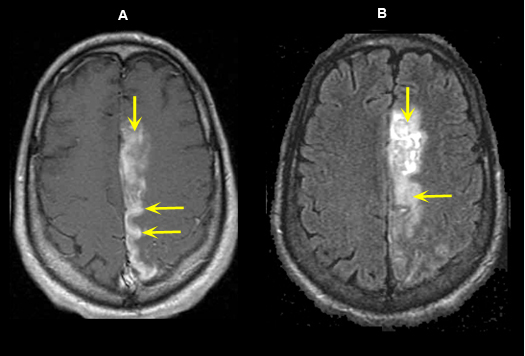

Figure 6: MR Images

Left Anterior Cerebral Artery Territory Acute Infarction (5 days old)

Imaging findings: Figure 6

- Post-contrast axial T1 wtd. image demonstrates gyral enhancement (yellow arrows) involving the territory of left anterior cerebral artery.

- Flair image shows an area of increased signal (yellow arrows) related to acute infarct.